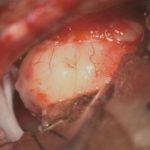

707

'25年12月

80代

髄膜腫

頭蓋内腫瘍摘出術

No.’25_109 手術前1

No.’25_109 手術前2

No.’25_109 摘出 前

No.’25_109  摘出 中

No.’25_109 摘出 後